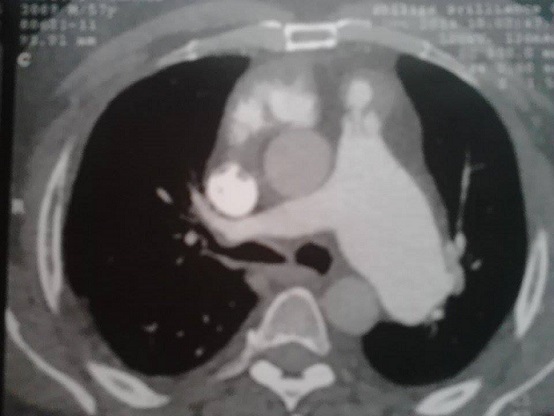

La sclérodermie systémique est une pathologie auto-immune non spécifique d'organe caractérisée par une sclérose cutanée qui peut être limitée aux doigts ou plus étendue. L'atteinte pulmonaire est le principal facteur de mauvais pronostic. L'hypertension artérielle pulmonaire primitive et l'atteinte interstitielle souvent à type de fibrose en sont les expressions les plus fréquentes. Patient de 53 ans chez qui le diagnostic de sclérodermie systémique a été porté devant des antécédents de nécrose digitale, un syndrome de Raynaud, une sclérodactylie, une hypertension artérielle pulmonaire (68mmHg) à l'échographie cardiaque et des anticorps antinucléaires positifs (fluorescence nucléolaire) à 1/80. Dans le cadre de la recherche d'une atteinte pulmonaire interstitielle et en dehors de toute symptomatologie respiratoire, une radiographie du thorax montrait une opacité médiastinale ronde de tonalité hydrique bien limitée en regard de l'arc moyen gauche. A ce stade, les diagnostics évoqués étaient un cancer broncho-pulmonaire (qui a une incidence élevée au cours de la sclérodermie), une adénopathie médiastinale et un anévrysme de l'aorte. Un complément d'angio-scanner thoracique objectivait une dilatation anévrysmale de l'artère pulmonaire gauche d'environ 47mm. L'abstention thérapeutique et la surveillance régulière étaient préconisées. Des anévrysmes de l'artère pulmonaire ou de ses branches ont été rapportés chez des patients atteints d'une hypertension artérielle pulmonaire. Le rôle d'une macroangiopathie n'est cependant pas exclu, puisque d'autres localisations anévrysmales aortiques etcérébrales ont été décrites chez des patients sclérodermiques. Ailleurs, les anévrysmes des artères pulmonaires peuvent être d'origine néoplasique, infectieuse, iatrogène (cathétérisme cardiaque) ou secondaire à une vascularite systémique (surtout la maladie de Behçet).